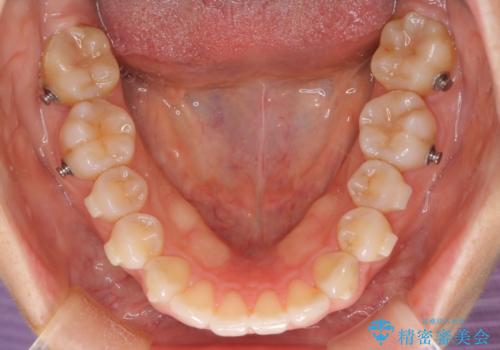

- インビザライン

- 1年6ヶ月

スペースを作るために顎間ゴムを使用して、奥歯の遠心移動をおこない配列しました。